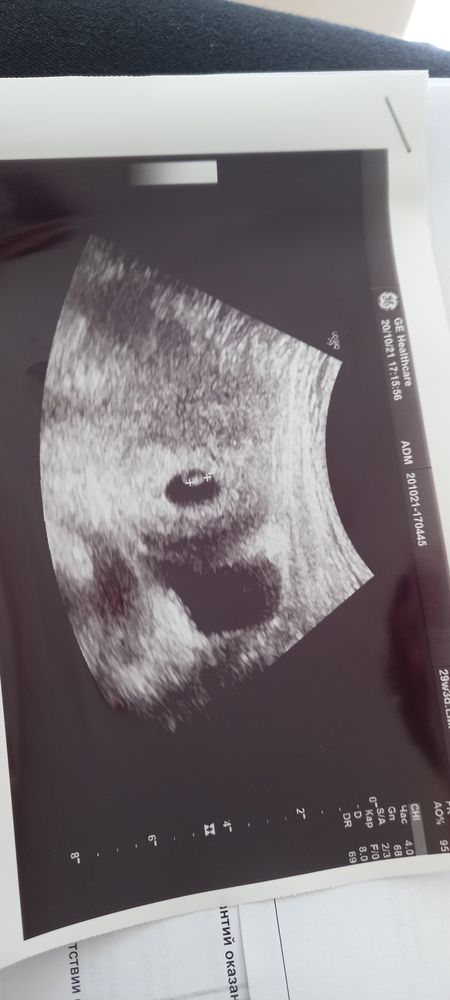

Узи 7 недель

Ой, девочки , я сегодня довольная)) 6 дней назад ходила на узи, написали 4н 3 дня, сердцебиение не визуализируется. Сегодня пошла к моему любимому и самому лучшему специалисту в городе . 6 н 2 дня по узи ( по мес. 6 н. 6д) , сердечко стучит, ктр 5мм))) не пойму , за 6 дней так выросли, или на прошлом узи узистка ошиблась... Даже фоточку дал, хотя, я не просила )) вообщем, надеюсь , еще месяц до 1 скрининга спокойно буду ходить, а то после ЗБ 3 года назад паника до сих пор не покидает...